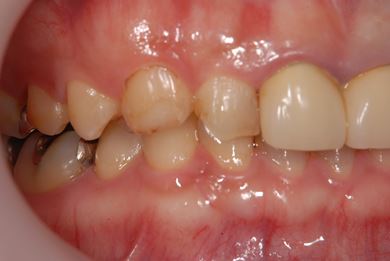

| 性別/年齢 | 女性 / 30歳 | ||||||||||||||||||||||||||||||||

| 主訴 | 上の奥歯を抜歯すべきかどうか、抜歯する場合はインプラント治療が可能かどうかの相談。 | ||||||||||||||||||||||||||||||||

| 治療方針 | ソケットリフトにて上顎洞を拳上し、インプラント治療を可能にする。 | ||||||||||||||||||||||||||||||||

| 治療内容 | インプラント2本(ソケットリフト)、メタルボンドセラミッククラウン1本 | ||||||||||||||||||||||||||||||||